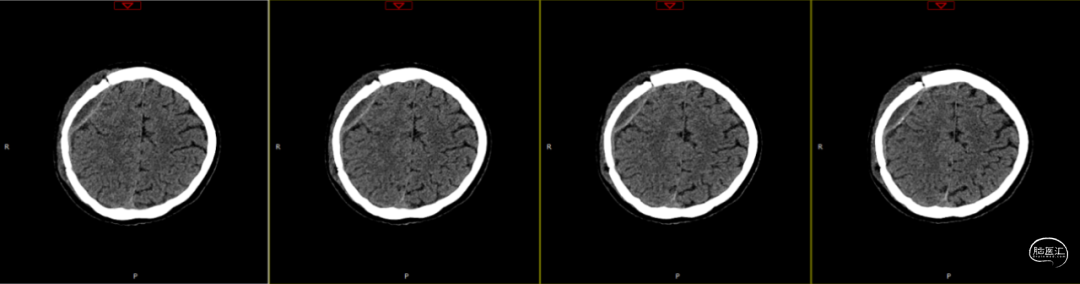

查体:嗜睡-昏睡状态,精神差,刺激睁眼,简单应答,肢体活动简单从嘱。GCS13分。双侧瞳孔等大等圆,直径2.5mm,对光反射灵敏,伸舌欠合作。转头、耸肩欠合作,四肢肌力4级,肌张力正常,颈抵抗(+),双Babinski sign未引出。枕部可见约5*4cm皮下血肿,压痛,拒按。周身多发片状皮肤擦伤。颅脑CT:双侧额叶脑挫裂伤;右侧顶颞枕部硬膜外、硬膜下血肿;蛛网膜下腔出血;右侧颞骨骨折累及右侧人字缝、顶乳缝,右侧顶乳缝旁小骨片;头皮软组织损伤、局部皮下血肿;双肺挫伤可能。

因患者在病情观察期间意识状态变差,昏睡-浅昏迷状态,予以急症手术治疗,清除硬膜外血肿,鉴于术中脑组织压力不高,予以骨瓣回置,术后严格控制血糖水平,常规使用抗生素(头孢唑林钠)预防感染。

术后第1天颅脑CT复查(如上图)